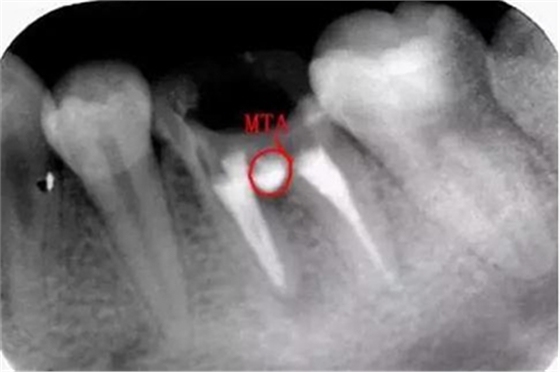

沖洗后封閉氫氧化鈣一周后MTA修補:

一周后:

MTA:有點太貴啦,這個病號是個在校的大學(xué)生統(tǒng)統(tǒng)的費用700,專門為他訂購的材料,我真的盡力啦。

修補后:

沒有顯微鏡和MTA輸送器做的有點不精致,幸好還有個放大鏡要不更累啦。